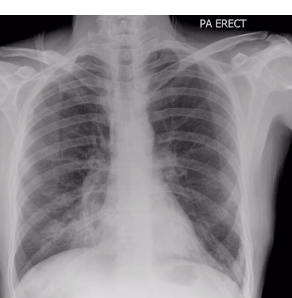

label this bestie xox